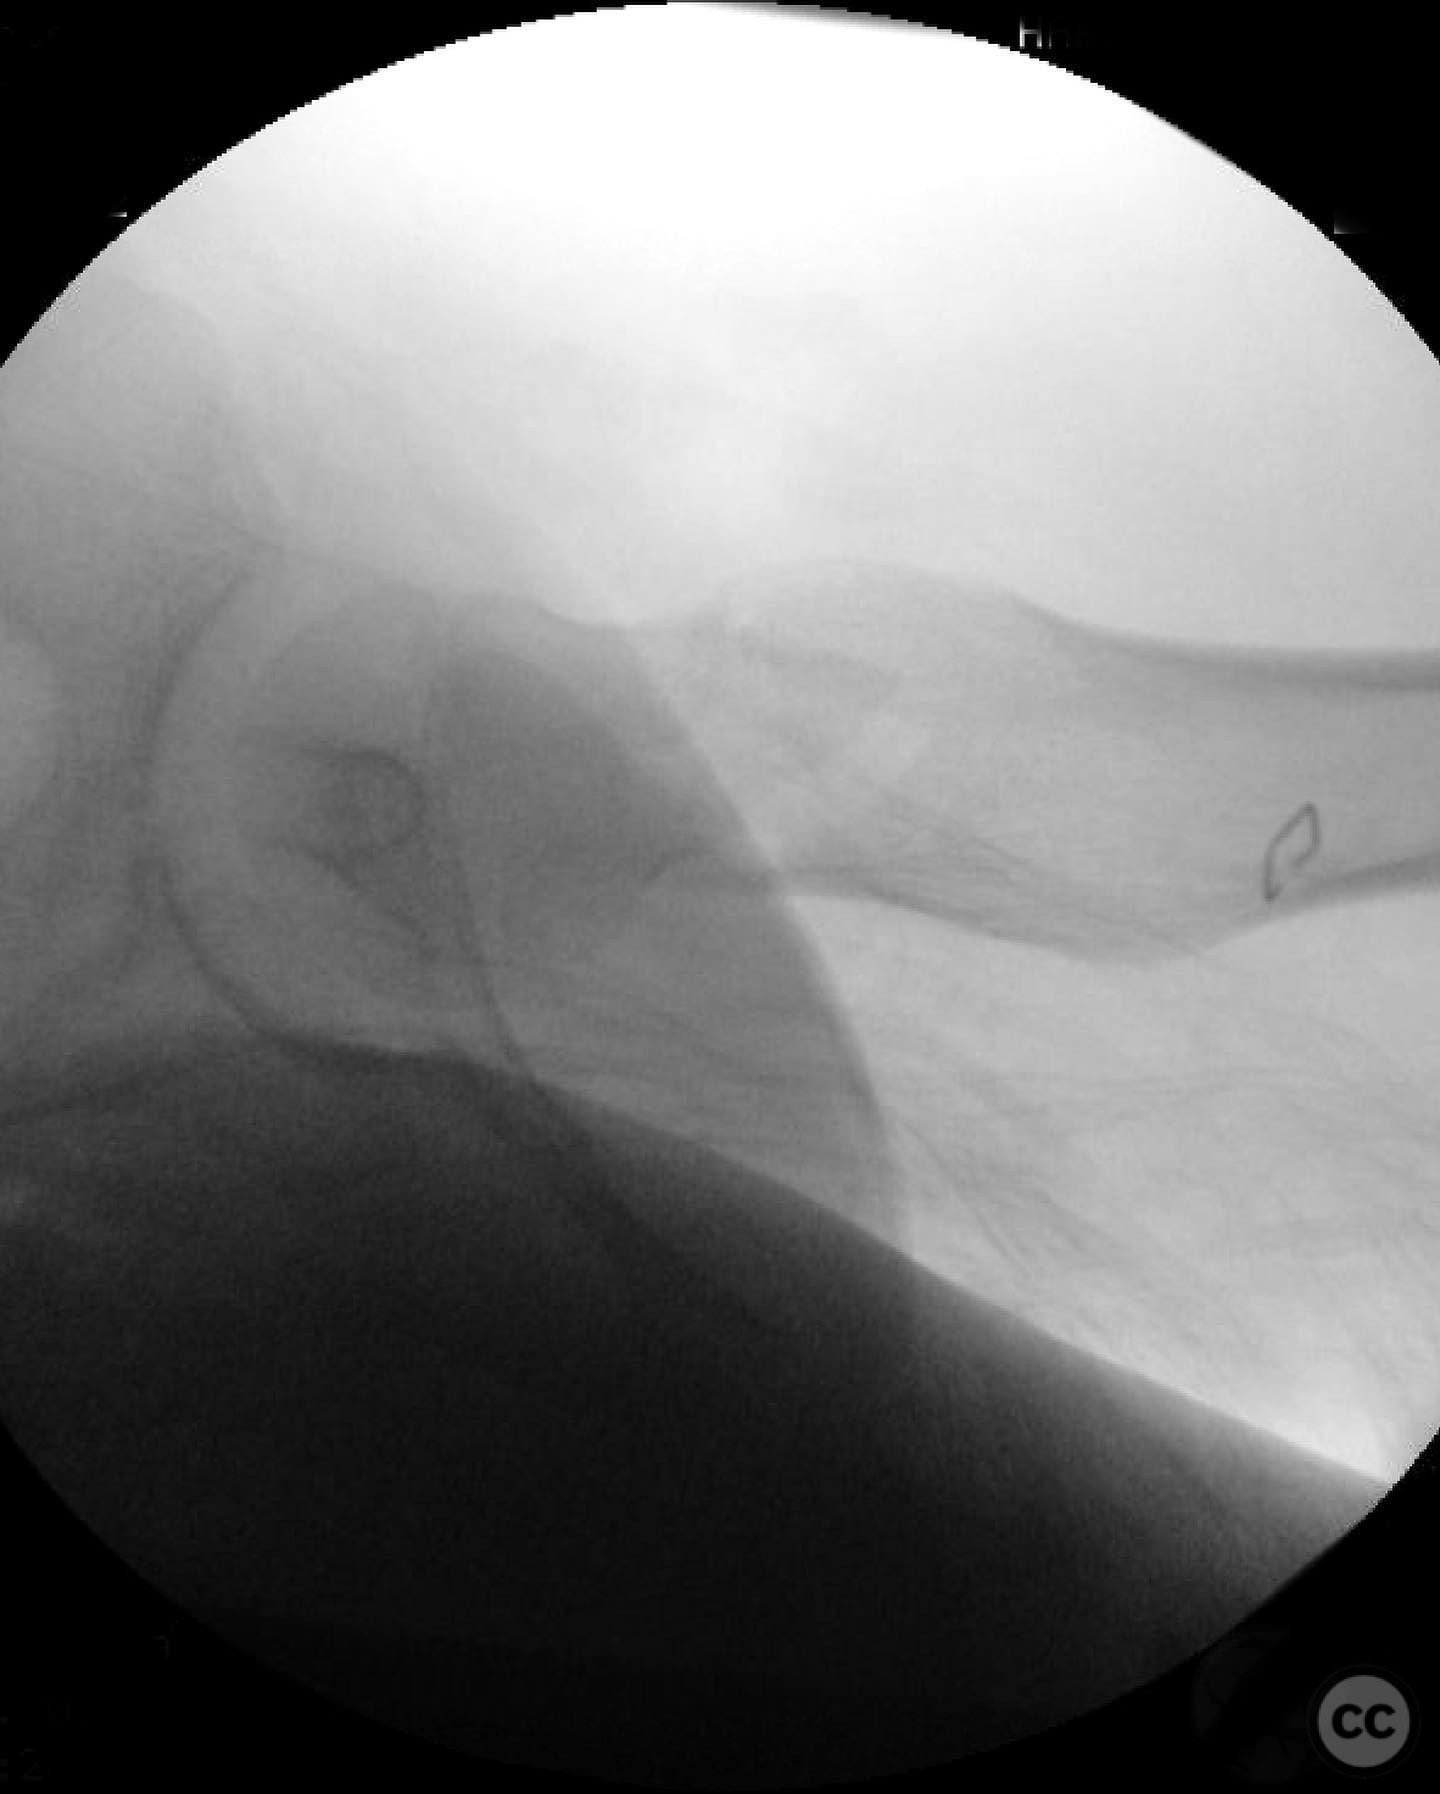

Anatomical surgical approach:  A modified Smith-Petersen approach was utilized, involving an incision along the anterior aspect of the hip, allowing for direct visualization of the femoral neck. Subperiosteal dissection was performed to expose the fracture site without compromising the surrounding musculature. A separate lateral approach was employed for the application of fixation devices.

Operative remarks:

The surgeon emphasized the importance of achieving a high-quality reduction and stable fixation due to the displacement pattern of the fracture. A meticulous surgical approach was critical to avoid malreduction, which is not well-tolerated in pediatric patients. The modified Smith-Petersen approach provided excellent visualization for anatomic reduction, minimizing soft tissue damage.

Orthopaedic implants used:   Angle stable static device (specific brand not mentioned).